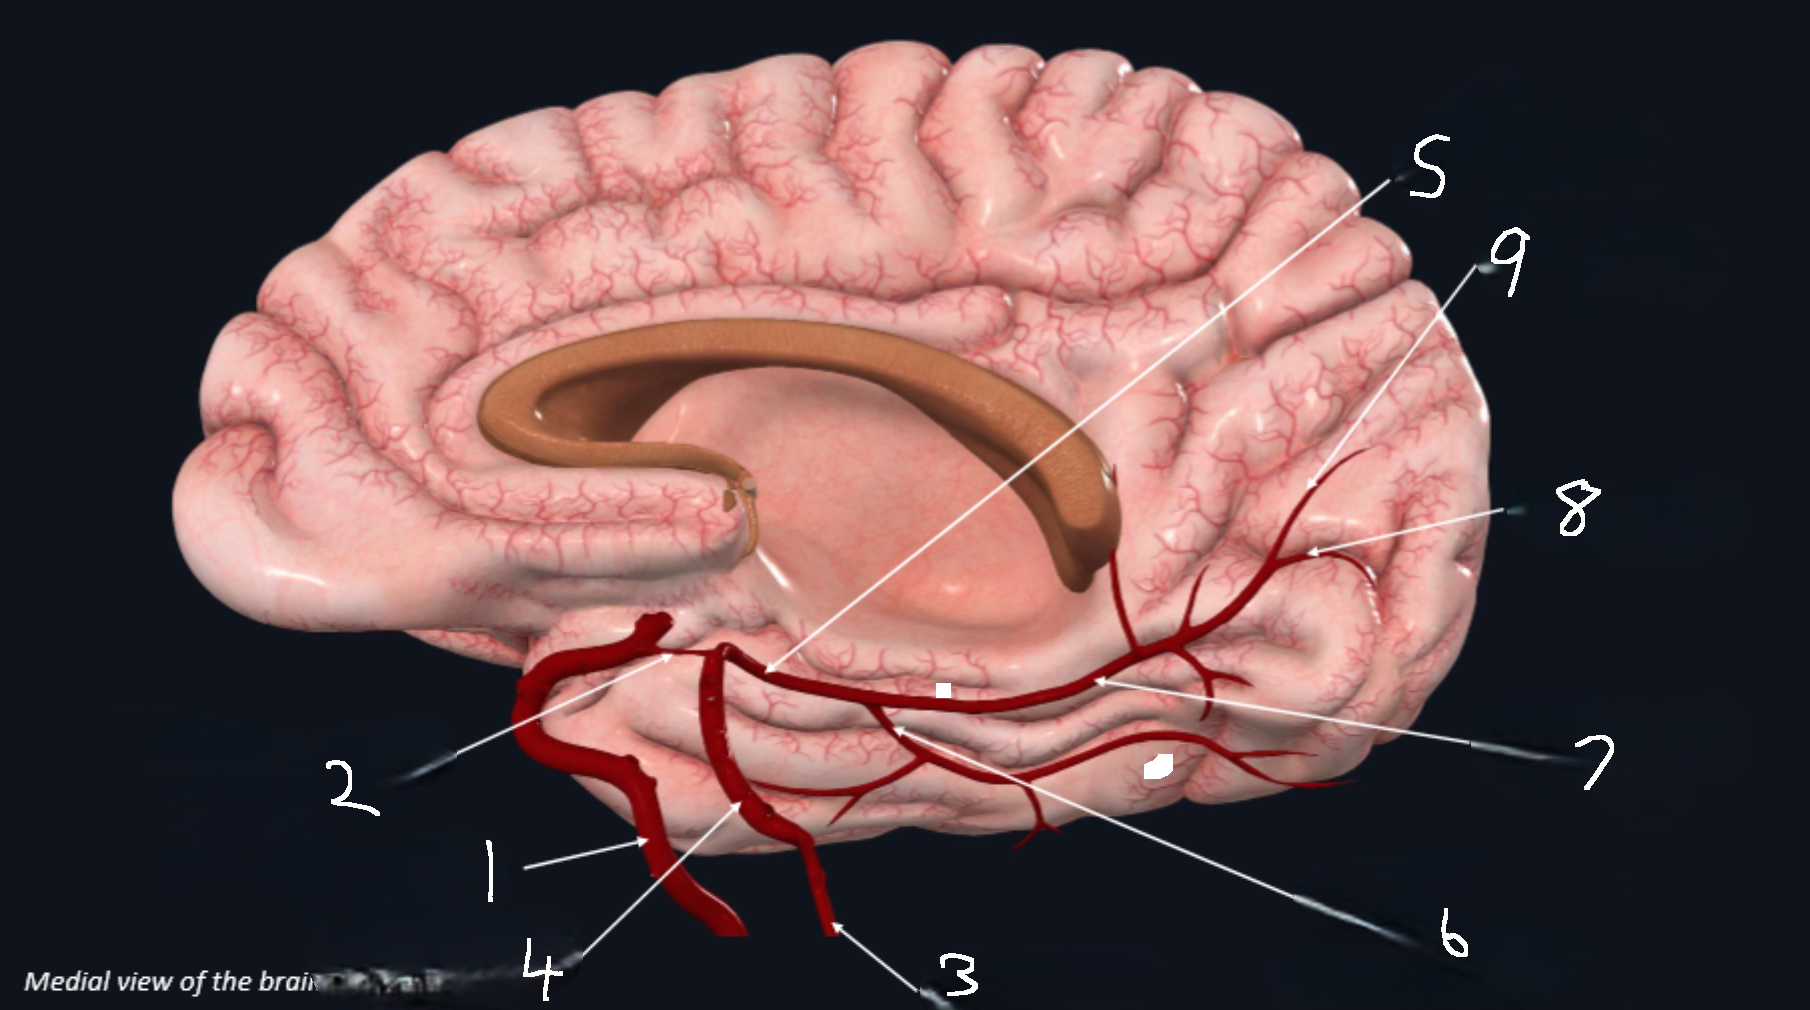

What is 1?

internal carotid artery

What is 2?

anterior cerebral artery

What is 3?

frontopolar artery

What is 4?

pericallosal artery

What is 5?

callosomarginal artery

What is 6?

corpus callosum